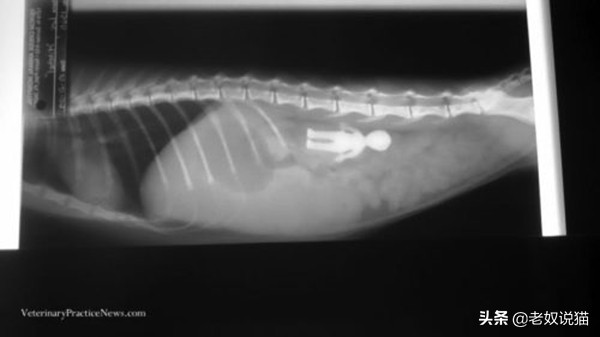

三、误食电线的猫

一只18个月大的小猫肚子中的电线